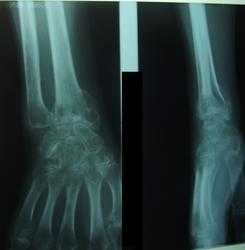

ЗУДЕКА АТРОФИЯ ЗУДЕКА АТРОФИЯ (Sudeck) острая костная, заболевание, описанное 3., который, основываясь на изучении скелета рентгеновскими лучами, в 1900 г. установил, что при остром воспалительном заболевании костей и суставов быстро наступает костная атрофия. В 1901—02 гг. Зудек доказал, что острая костная атрофия возникает не только при воспалительных состояниях костей и мягких тканей, но и после травматических повреждений. Тогда же Зудеком была выдвинута теория, считающая рефлекторный трофоневроз* причиной острой атрофии, и потому автор назвал такое состояние костей «острой рефлекторной костной атрофией». Помимо рефлекторной теории Зудека были выдвинуты и другие причины как этиологический момент острой костной атрофии. Среди них теория атрофии от бездеятельности (Inaktivitatsatrophie) поддерживалась особенно Брандесом (Brandes). Противники теории трофоневроза и сторонники теории атрофии от бездеятельности видят причину атрофии в расстройстве питания вследствие уменьшенной доставки питательных веществ. В работах Кинбёка, Кёлера, Эмбдена (Kienbock, Kohler, Embden) вопрос об острой костной атрофии подвергся более детальному изучению. Среди внешних причин развития острой костной атрофии отмечаются: острое и хрон. воспаление костей и суставов, панариций, флегмона сухожильных влагалищ, травмы различного рода и размозже-ние мягких тканей, контузии и дисторсии суставов, переломы костей и суставов, вывихи; далее атрофии отмечаются при повреждении нервов, при нек-рых кожных заболеваниях (herpes zoster), при периферических и центральных страданиях нервной системы. Из хрон. заболеваний суставов на первом месте стоит tbc. Костная атрофия при туб. артри- тах появляется сравнительно рано, когда еще может не быть грубых деструктивных изменений, и в сочетании с клин, картиной служит важным признаком воспалительного состояния сустава. Острые артриты, особенно—гоноройные и септические, нередко сопровождаются костной атрофией. В отношении травмы еледует отметить интересную особенность: травма может быть незначительной, но вызывает значительную костную атрофию. Рано появляется атрофия при отморожениях и ожогах. Срок возникновения атрофии от момента заболевания или повреждения различен—от 4 г /2 до 10 недель. При отморожении Гичман и Вахтель (Hitschmann, Wachtel) установили атрофию спустя 14 и 25 дней. После травмы кисти наблюдали ясно выраженную костную атрофию спустя 672 недель. Трудно точно установить период возникновения атрофии при туб. артритах, т. к. невозможно клинически и рентгенографически определить момент заболевания сустава туберкулезом. Пат. анатомия острой костной атрофии сравнительно мало изучена. Экснер (Ехпег) установил, что вес атрофических костей значительно понижен: в одном из его случаев—на 30%, в другом—на 7%, в третьем—на 67 %. Натаниель и BpyKc(Natha-niel, Brooks) экспериментально установили следующее. Периост отделяется с трудом, corticalis делается порозной. Толщина кортикального слоя уменьшается при одновременном расширении костномозгового канала, костные балочки значительно истончаются и уменьшаются количественно. Другими исследователями установлено повышение колич. остеокластов, под влиянием которых происходит усиленный процесс резорпции при слабой аппозиции. Следовательно рентгенографически атрофия хорошо устанавливается не только вследствие потери солей, но также и вследствие исчезновения основного вещества кости. Эти процессы идут параллельно: уничтожается основное вещество, и освобождающиеся соли резорбируются. Явления острой костной атрофии вырисовываются раньше и ярче на спонгиозных костях в дистальных сегментах конечностей и рельефнее всего устанавливаются рентгенографически на кисти и мелких костях стопы. Но явления атрофии несомненно имеют место и в центральных отделах скелета и даже вдали от основного очага или участка непосредственного травматического повреждения.—Рентгеновская картина. 3yj дек различает рентгенологически острый и хрон. стадии атрофии. Начальный стадий, по Зудеку, характеризуется неравномерным пятнистым просветлением, и эту пятнистость Зудек считает характерным признаком острой рефлекторной костной атрофии. Дальнейшими работами других авторов установлено, что пятнистость не является характерной для определения типа атрофии: она отмечается при всякой костной атрофии, возникающей сравнительно быстро,иобъясняет-ся пат.-анат. особенностями. Процесс резорпции, начинаясь с костномозговых и Гаверсо-вых каналов, ведет к узуре, истончению и полному исчезновению отдельных балочек на определенном участке кости, тогда как зюсмильх остальная субстанция сохраняет временно нормальную структуру. Такие участки ре-зорпции и получаются на рентгенограмме в виде пятнистых просветлений. Кроме пятнистости на рентгенограмме отмечается неясность структуры балочек, снимок как бы «смазан». В хрон. стадии костной атрофии отмечаются резко очерченные контуры при истончении кортикального слоя. Клин, картина. При острой костной атрофии наблюдаются одновременно ат-рофические изменения со стороны мягких тканей, кожи, мышц. В последних отмечается понижение электровозбудимости. В большинстве случаев появляется отечное состояние на кисти и стопе, почти всегда имеются вазомоторные расстройства, цианоз с субъективными и объективными признаками местного понижения t°. Боль и расстройство функции являются почти постоянными признаками, причем болезненность может сохраняться даже тогда, когда прочие признаки уже исчезли. Особенно характерная картина такой атрофии с длительной болезнен-но.стью отмечается в нек-рых случаях при переломах луча (loco classico) и в отдельных случаях переломов в пределах голенностоп-ного сустава и стопы. Важным обстоятельством при атрофии костей является их хрупкость и возможностьпереломаприминималь-ном инсульте. Легко возникают переломы шейки бедра и супракондилярные переломы. Ортопедам известны также летальные случаи жировой эмболии при редрессации атро-фических стоп. — Специфического лечения для костной атрофии не имеется. Необходимо устранение и лечение основного заболевания.Приповреждении кисти и пальцев желательно стимулировать больного к ранним активным движениям. От пассивных движений и грубого массажа, вызывающего боль, следует воздержаться. При переломах ранние движения могут до известной степени предупредить развитие костной атрофии. Легкий, безболезненный массаж, суховоздушные ванны, относительный покой больной конечности ведут к улучшению. Для лечения костной атрофии при переломах radii loco classico Турнером предложена резекция п. interossei dorsalis. Когда атрофия поддерживается вследствие бездеятельности конечности, необходимо создать условия (путем шин или аппарата) для нагрузки, если они не вызывают боли. При tbc костная атрофия сохраняется длительно. По окончании процесса желательно поставить конечность в условия относительной физиологической нагрузки. Лит.: Beck О., Die pathologische Anatomieund spezielle Pathologie der Knochenatrophie, Erg. d. Cnir., B. XVIII, 1925 (лит.); S u d e с k P., "Ober die akute entziindliche Knochenatrophie, Arch. f. klin. Chirurgie, B. LXII, 1900; о н ж е, tjber die akute (reflektorische) Knochenatrophie nach Entziindungen u. Verletzungen an den Extremit&ten u. ihre klinische Erscheinungen, Fortschritte a. d. Geb. d. ROntgen-strahlen, B. V, 1901—02. В. Чавлин.

Проницаемость сосудистой стенки нарушается. Формируются микроциркуляторные расстройства, метаболический ацидоз, тканевая гипоксия. Все перечисленное приводит к раздражению нервных окончаний, появлению болей, образованию очагов рассасывания костного вещества. На рентгенограммах обнаруживается характерная картина «пятнистого остеопороза».

- Рентгенография. На снимках обнаруживается типичный «пятнистый» остеопороз, при предшествующем переломе выявляются признаки костной мозоли.

В классическом варианте РСД развивается в результате длительного отсутствия движений в соответствующих суставах конечностей (чаще кистей и стоп) при травмах и ожогах. В области пораженных суставов появляются боль, отек, отмечаются повышение температуры и потоотделения, синюшность кожи, которая становится тонкой и лоснящейся, ограниченная подвижность одного или нескольких суставов, атрофия мышц. Имеют место нарушения чувствительности (по типу гиперестезии, аллодинии и др.). На рентгенограммах выявляется выраженный остеопороз.

Классическим рентгенологическим признаком РСД является выраженный пегий (или пятнистый) остеопороз, выявляемый обычно на 3-4-й неделе от начала заболевания у 80% больных, при длительном течении переходящий в диффузный остеопороз.